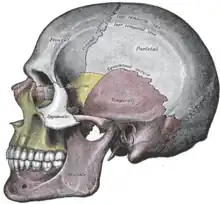

L'os temporal est un os pair du crâne situé dans la région de la tempe, sur la partie latérale de la tête. Il participe à la formation de la voûte de la base du crâne. Il accueille aussi l'articulation temporo-mandibulaire, les organes de l'audition avec la caisse du tympan et de l'équilibre avec le vestibule et la cochlée.

Son anatomie est réputée une des plus complexes de tous les os du corps humain et on peut l'aborder sous plusieurs perspectives : du point de vue de ses faces endocrânienne et exocrânienne et de ses quatre bords, ou du point de vue de ses composantes issues plus ou moins de ses origines embryologiques.

L'os temporal résulte de la fusion de trois os qui se soudent dans l'adolescence : l'os squamosal, l'os tympanal et l'os pétreux qui gardent comme trace de séparation un fin sillon sur la surface de l'os. Mais on a l'habitude pour le décrire de le séparer en trois parties qui ne correspondent pas à la formation de l'os. C'est ainsi qu'on distingue :

- l'écaille de l'os temporal qui correspond à la plus grande partie de l'os squamosal ;

- la partie pétreuse de l'os temporal et la partie tympanique de l'os temporal qui correspond à l'os tympanal et à une partie de l'os pétreux ;

- la portion mastoïdienne de l'os temporal qui correspond à une partie des os squamosal et pétreux.